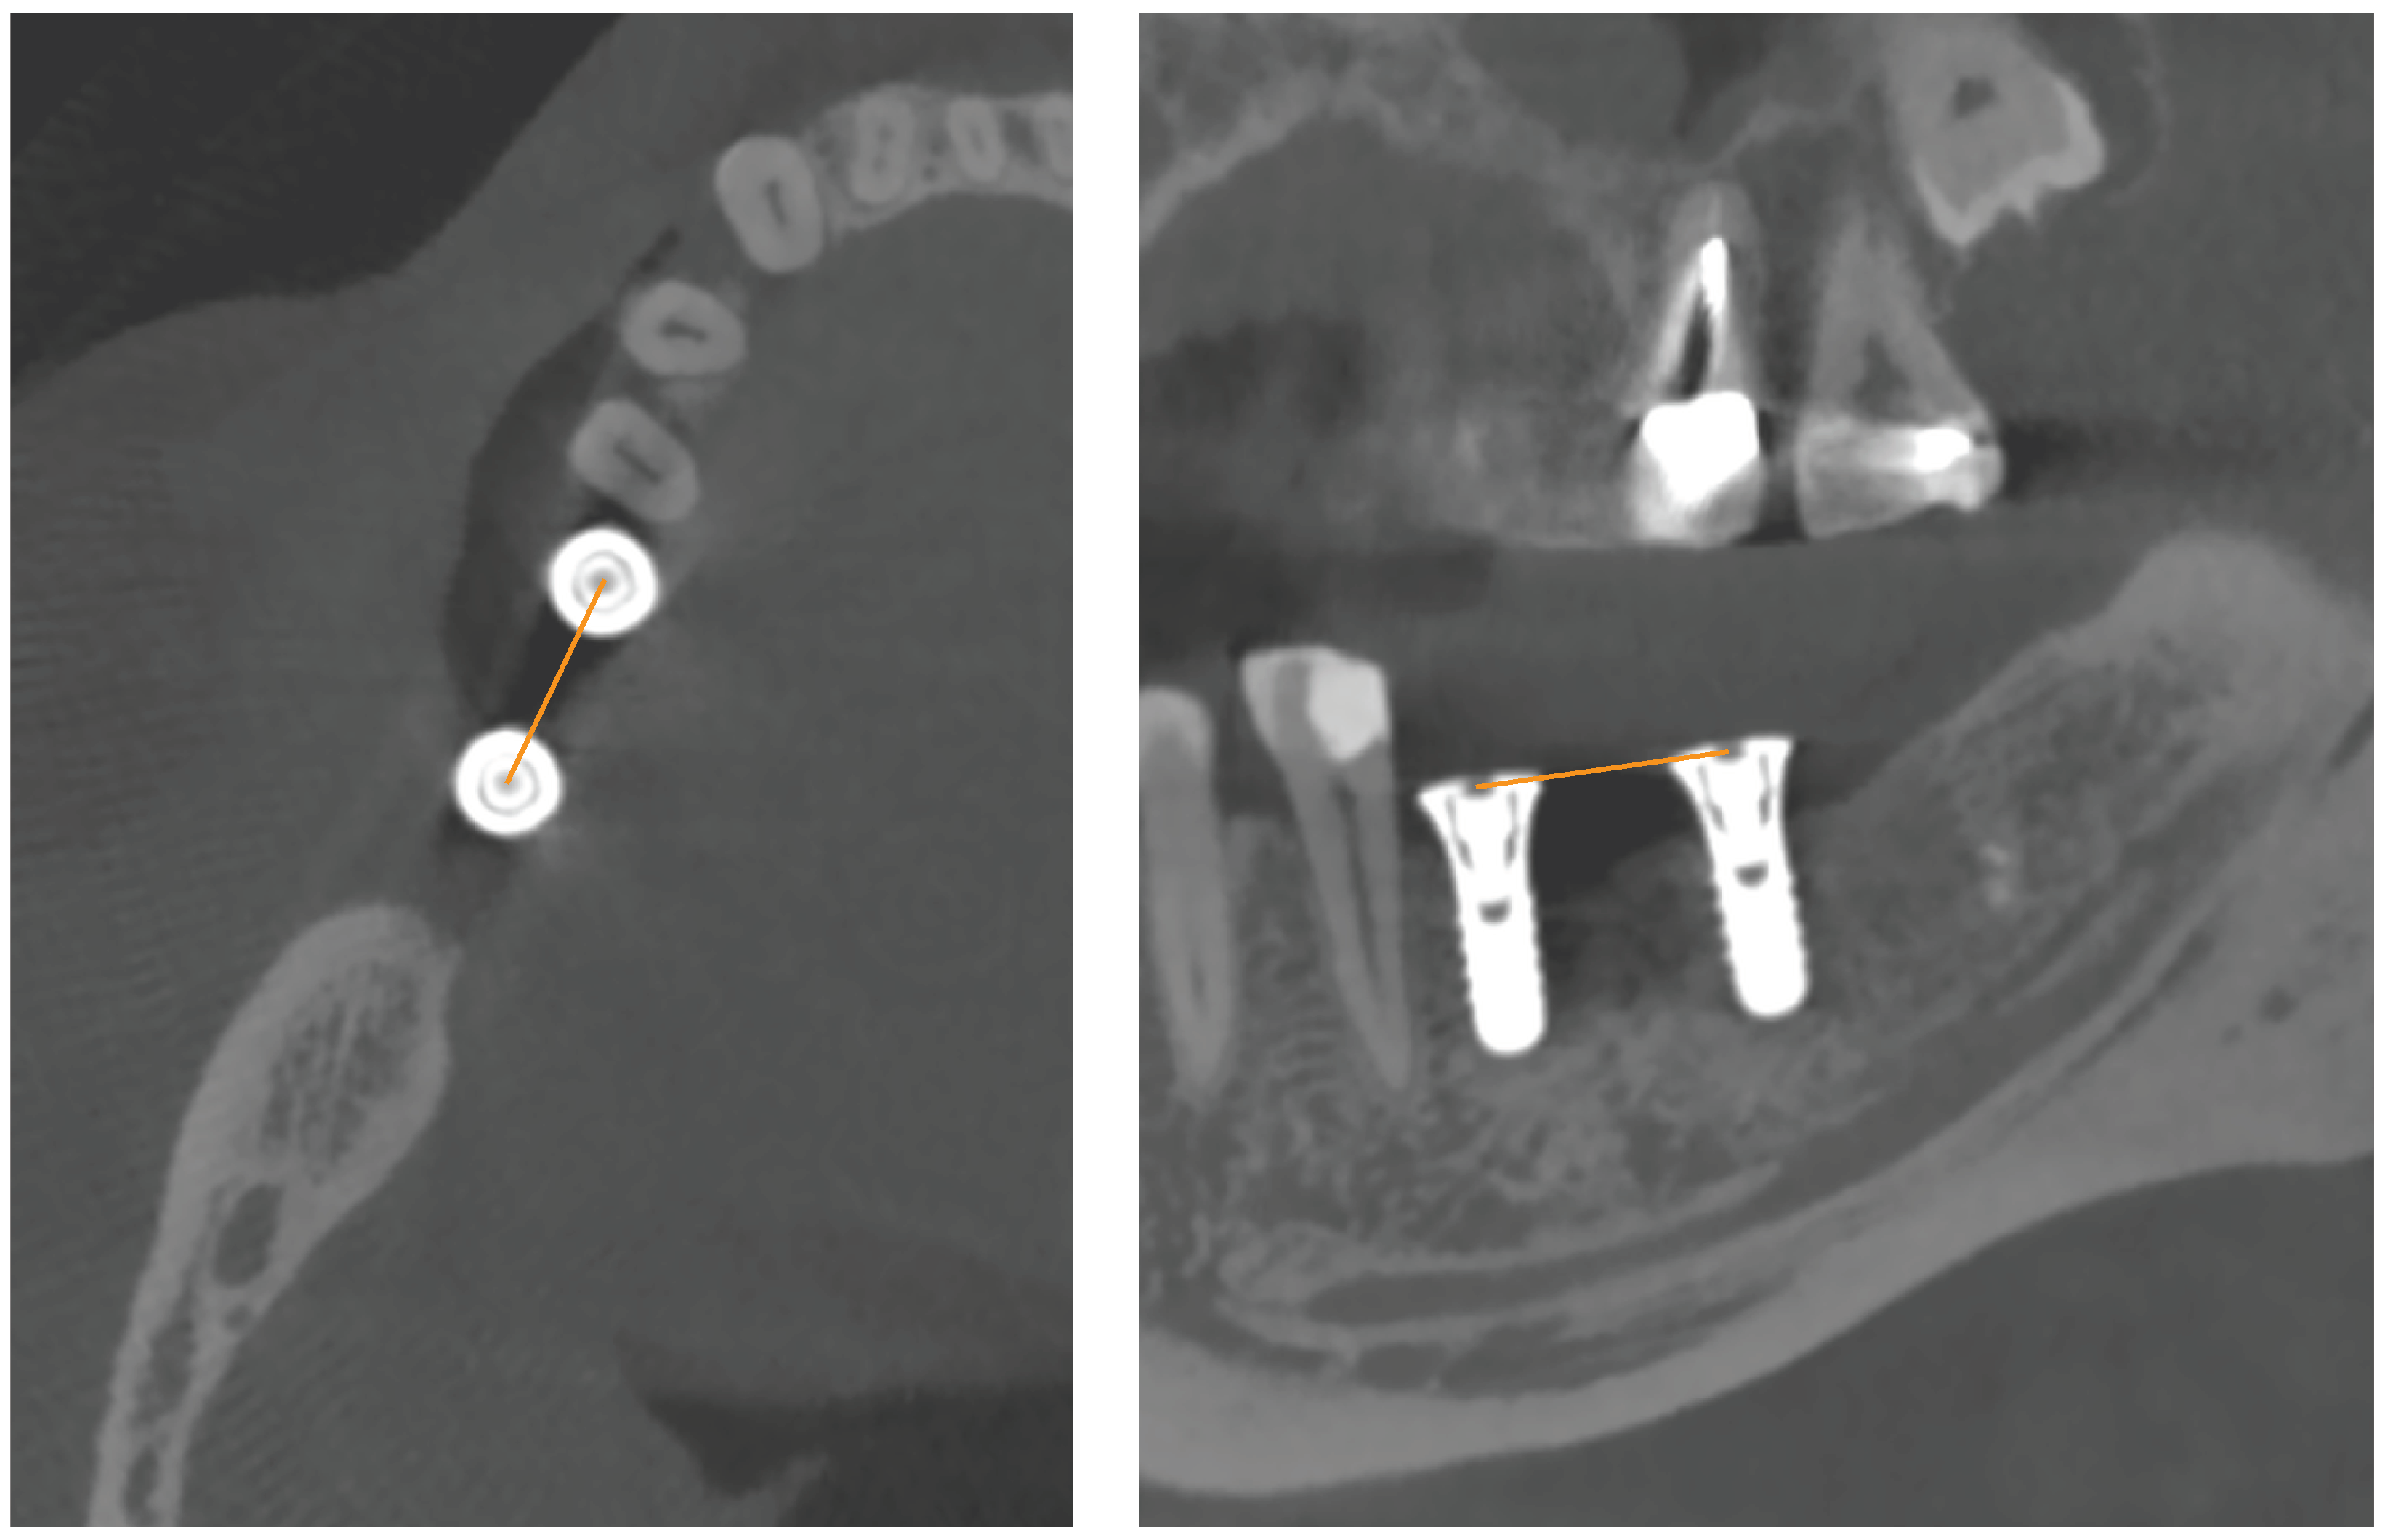

Postoperative CBCT imaging replaced postoperative intraoral or panoramic X-ray in this prospective study. After implant surgery, study participants were sent to the Geneva University Hospitals (Switzerland) for a CBCT (NewTom VGi, Quantitative Radiology, Verona, Italy). Images were acquired using high-resolution mode (voxel size: 0.15 mm; field of view: 12 × 8 cm), and exposure parameters were set to 110 kVp, 3–11 mA. On NNT viewer, primary reconstructions were made with an isotropic voxel (pixel size: 0.15 mm; slice thickness: 0.15 mm). The acquisition data were saved on the PACS Digital Imaging and Communications in Medicine (DICOM) server (512 × 512 matrix) and exported to a compact disc. Two observers (J.P.C. and L.V.: observers 1 and 2, respectively), experts in oral surgery and radiology, took the measurements twice; sessions occurred at least 2 weeks apart. Axial, sagittal in multiplanar reconstruction mode. On the axial view, the cross-reference lines were aligned with the center line between the implant healing caps to display the two implants side by side on the sagittal oblique (hereafter sagittal) view. On the coronal view, the cross-reference lines were oriented to view the center of both healing caps on the sagittal views. On the CBCT axial and sagittal views (Figure 1), the inter-implant distance (i.e., the distance from the center of one implant healing cap to another) was measured with OsiriX DICOM viewer (Pixmeo, Geneva, Switzerland) installed on an iMac OS X (Apple Inc., Cupertino, CA, USA) independent workstation with a 2560 × 1440 resolution LCD screen.

Figure 1. Horizontal linear measurements from the center of one implant healing cap to another (i.e., inter-implant distance) on CBCT axial and sagittal views.